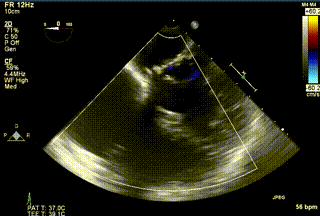

患者二术前心超

患者二术后心超